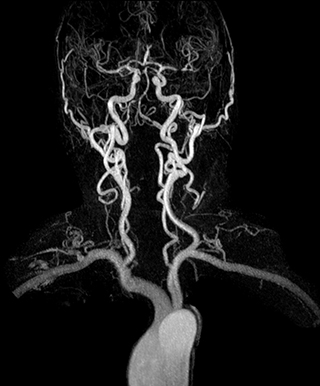

3D dynamic MRA of head and neck

Excellent image quality is obtained in this dynamic scan., C-SENSE factor 5.4, scan time is 1:20 min, voxel size is 0.8 x 0.8 x 1.6 mm, Ingenia Ambition, 1.5T.

Dynamic MRA of head and neck